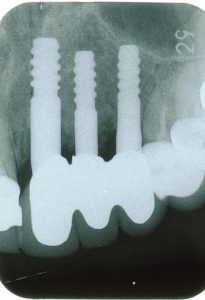

なぜならば、細いインプラント2本でブリッジにすると折れる可能性があるので、あえて3本埋入しました(パントモ5、デンタル3)。

(パントモ5) 細いインプラント2本でブリッジにすると折れる可能性があるので、あえて3本埋入しました。

(デンタル3)今回は骨移植などの侵襲性が大きい処置と、折れる可能性を回避し、日本製ハイドロキシアパタイトコーティングのインプラントを3本埋入しました。